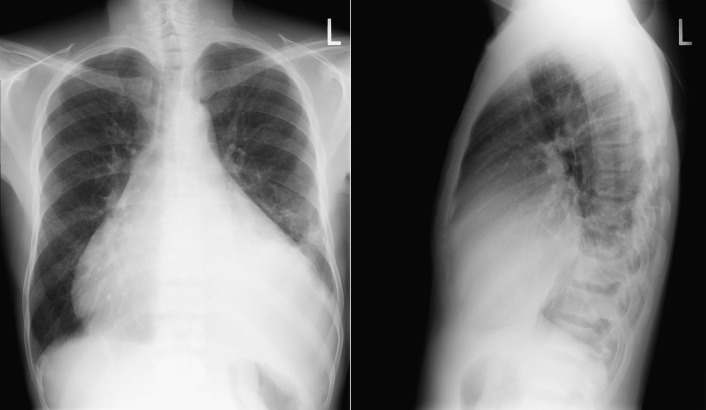

A pericardial effusion ( Figs. 16-1 to 16-15 ) is often suggested on the frontal chest radiograph by a smoothly distended, “flasklike” CPS. More than 500 mL of fluid must be present before the change in the CPS is fairly obvious. A flasklike appearance may be caused by myocardial disease as well; scrutiny of the hilar vessels may distinguish the two. In the presence of pericardial effusion, the hilar vessels are covered (the pericardium runs up onto them and obscures them). In the presence of myocardial disease, the hilar vessels are unusually prominent as they are distended under higher than usual pressure.

In a minority of patients with pericardial effusion, on the lateral radiograph, a stripe of radiolucent epicardial fat, a “fat line,” may be visible anteriorly, suggesting fluid in the pericardial space. A stripe greater than 2 mm is abnormal. This “pericardial stripe sign” is more easily seen in adults than children (more fat!).

A prominent azygous vein, superior vena cava, or inferior vena cava suggests cardiac tamponade.

Echocardiography is the diagnostic test of choice for the evaluation of pericardial effusions. Pericardial tamponade remains a clinical diagnosis, strengthened by supportive echocardiographic findings.